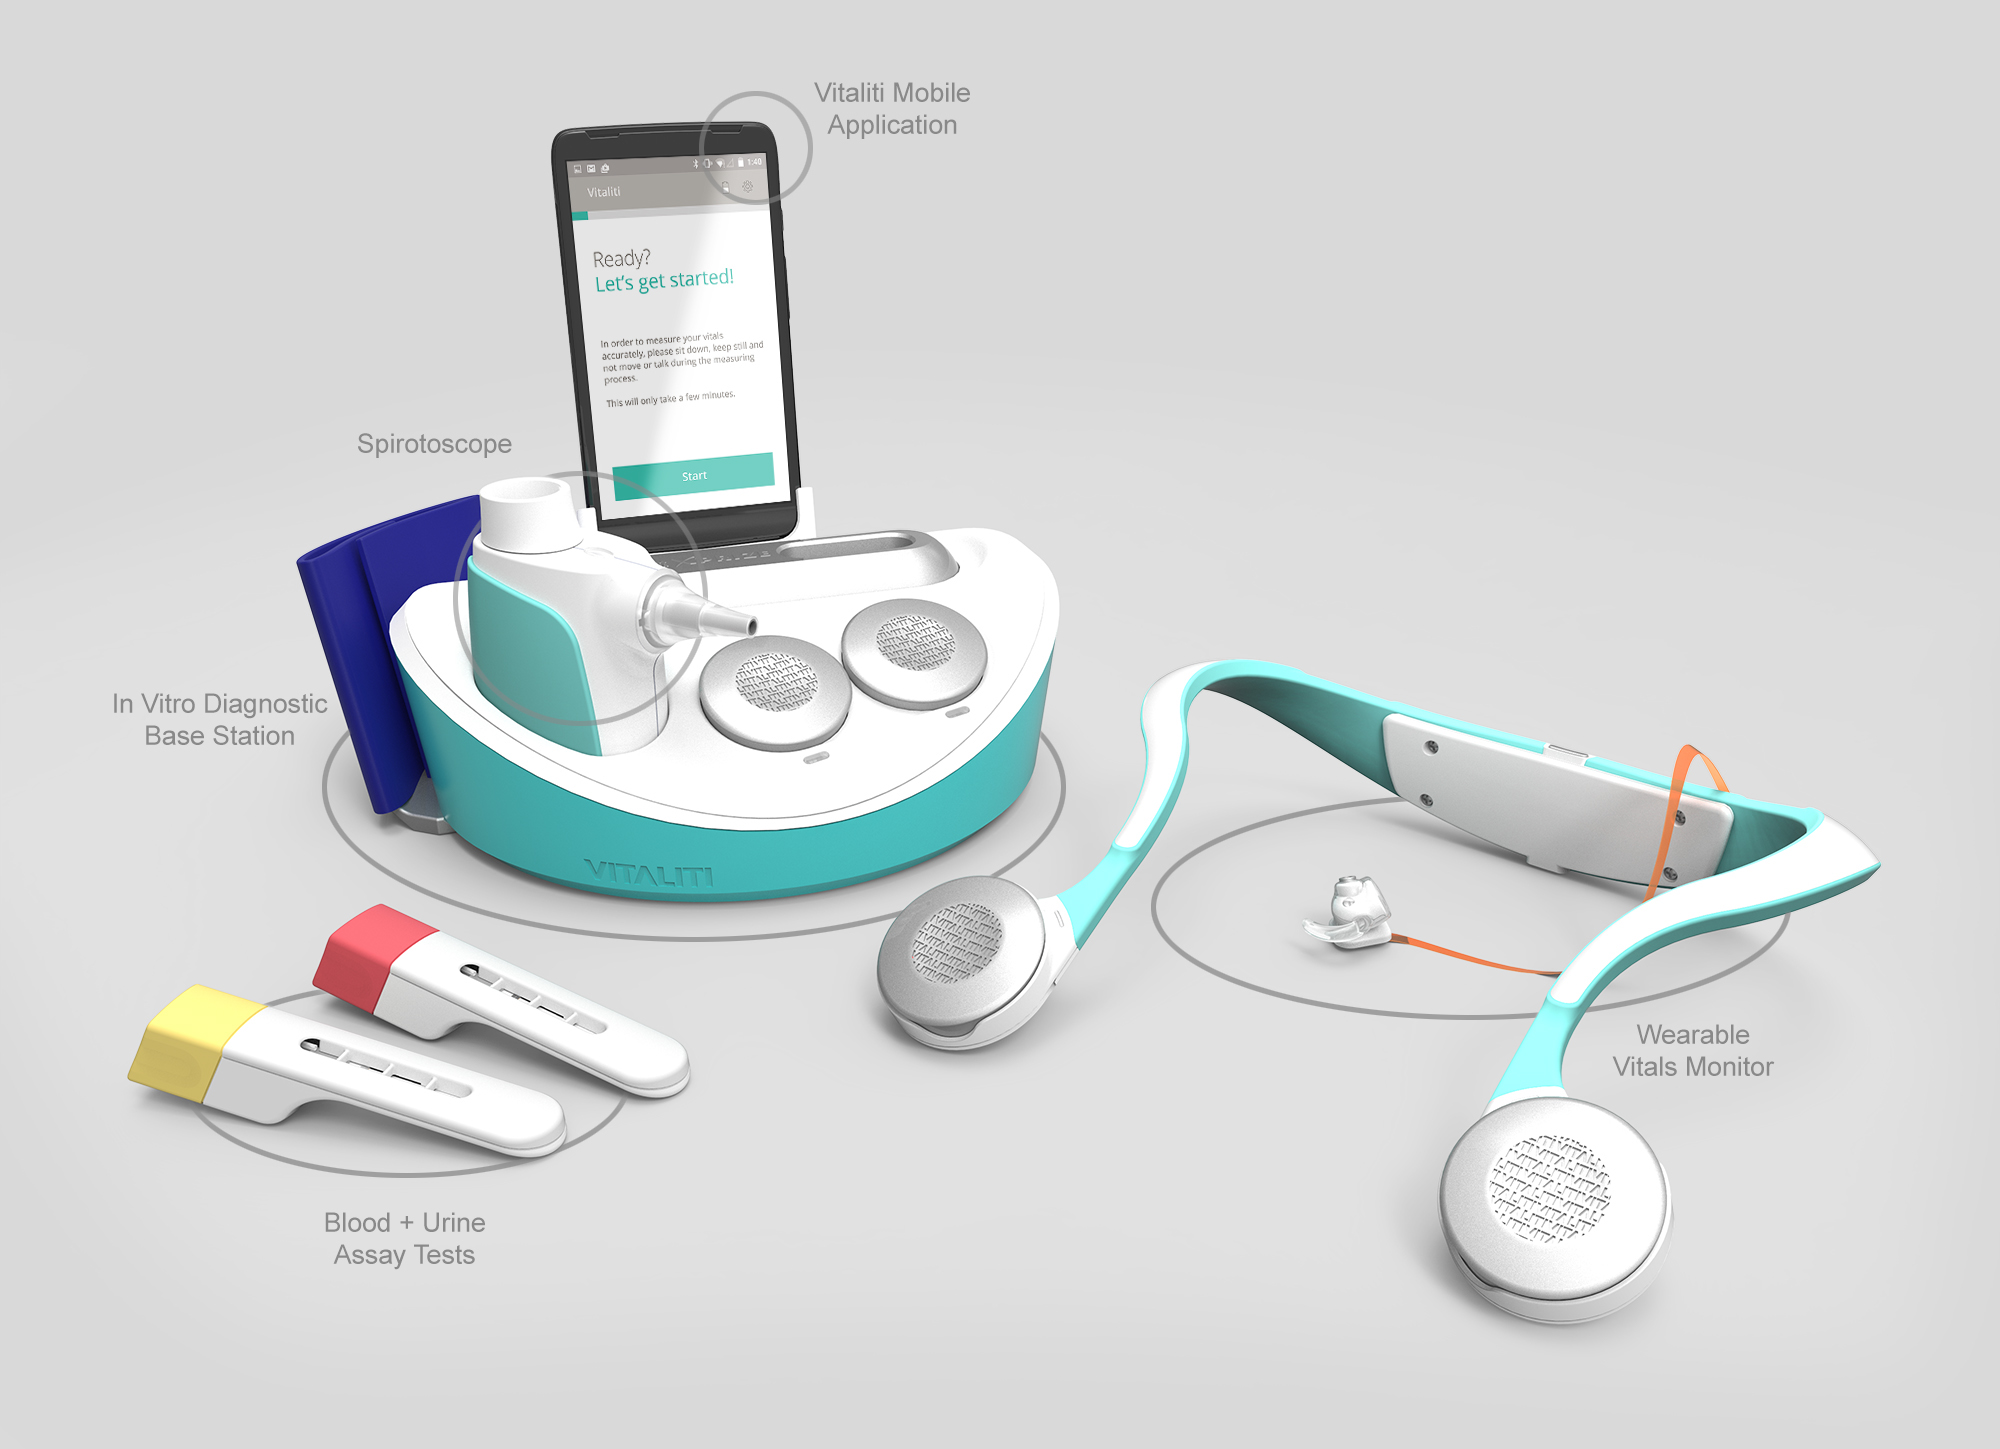

VITALITI is a “doctor in a box” – a wearable medical device paired with a diagnostic basestation that can diagnose 19 chronic medical conditions, monitor all 5 human vital signs, and stream that data to a cloud server – all without a clinician. And it had to weigh less than 5 lbs too. It is poised to disrupt overstressed healthcare systems and super-empower users by assessing physical wellness outside of clinical settings.

- How to bridge several data collection points on a patient’s collarbone and ear in a single wearable.

- The wearable had to collect all five human vital signs continuously for three days. We realized our wearable had to be easy to charge without the user having to take it off.

- Our system needed a diagnostic reader with controlled lighting to image cartridges. It also had to be small enough to fit within a five pound weight limit. A rotating loading mechanism kept the weight down and gave it Start Trek cred.

- Everything had to feel like an award winner. This ethos guided every decision as we designed the user experience